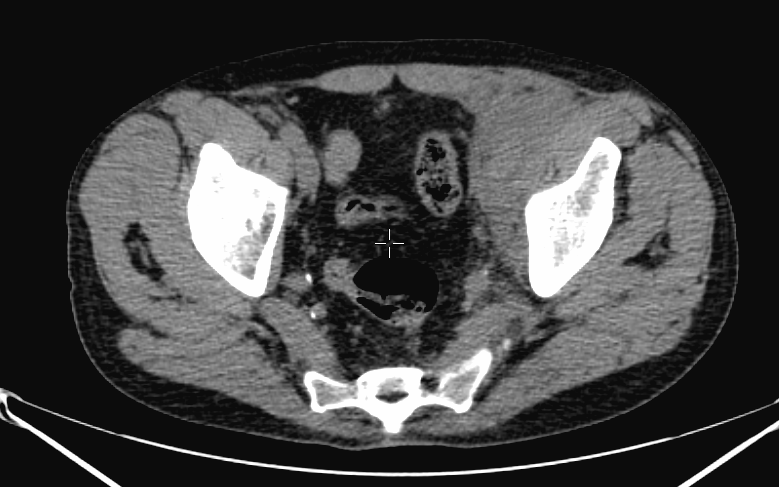

The most common indication of bone scintigraphy is the evaluation of bone metastasis. (Figure 5.)

5. Multiplex bone metastases. Bone scintigraphy, anterior (a) and posterior (b) whole body scans. SPECT-CT sagittal plane, fusion image (c) and CT image (d). Obvious bone structural changes cannot be identified on the CT scan yet.

The examination is appropriate for staging a malignant process and following-up bone metastases. It is clinically most suitable for lesions that frequently present bone metastasis, primarily in case of prostate-, breast-, lung cancer and neuroblastoma. It is, however only indicated in cases where the soft tissue involvement of the tumor is big enough to suggest a higher incidence of bone metastasis; before radical surgeries and for the selection of patients who would benefit form a palliative radionuclide therapy. Otherwise, scintigraphy is advisable in case of any primary tumor, if the suspicion for metastasis is raised, e.g.: bone pain, pathologic radiological or lab results (elevated serum ALP and tumor marker levels). Bone metastases in most cases are located in bones that contain red bone marrow (skull, vertebrae, ribs, sternum, pelvic bones and the proximal bone segments of the limb) and usually show a multiplex appearance. Activity increase can be seen typically, metastases that cause activity decrease are rare; they could occur in cases of thyroid gland tumor, renal carcinoma, lymphoma and multiple myeloma. Solitary lesions or a few lesions only, due to the aspecific nature of the examination, cause a differential diagnostic problem in many cases, for example vertebral degenerative processes can mimic metastatic activity. Equivocal lesions usually require further, targeted radiological investigations. A negative X-ray examination does not rule out the possibility of a metastatic lesion, since the isotope scan is more sensitive. Therefore, it is possible that it could already be detecting an existing metastasis, while X-ray is still insensitive and unable to show the lesion. (Figure 5.)

SPECT examination of the spine can help in the precise lesion localization within a single vertebra. It is especially useful, since the different pathologic bone processes occur in different predilection sites of the vertebral bone. Bone metastases are commonly located in the dorsal aspect of the vertebral body. Degenerative processes involve mostly the vertebral edge as in the case of spondylophytes in spondylosis. Finally, spondolyathrosis is usually located at the intervertebral facet joints.